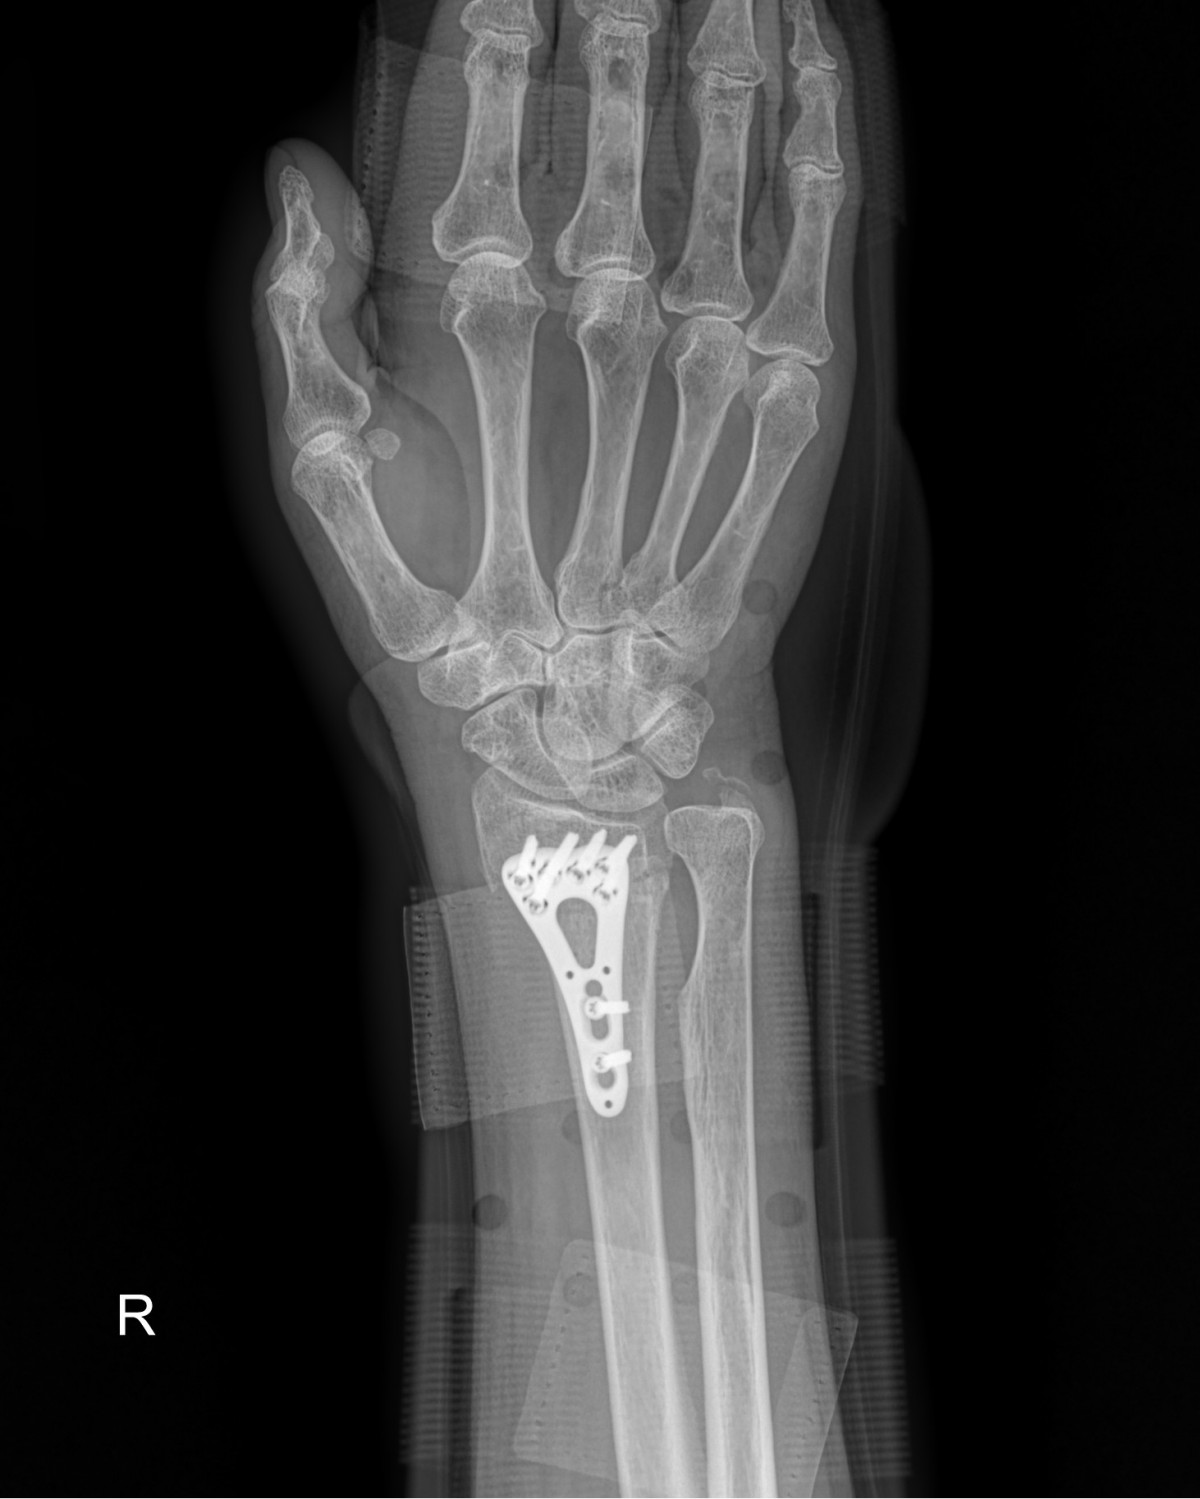

정지영원장님 손목 골절 수술 강복O 환자

dae765e4d9ac96aee867c9d6292d8784_1758008052_7917.jpg